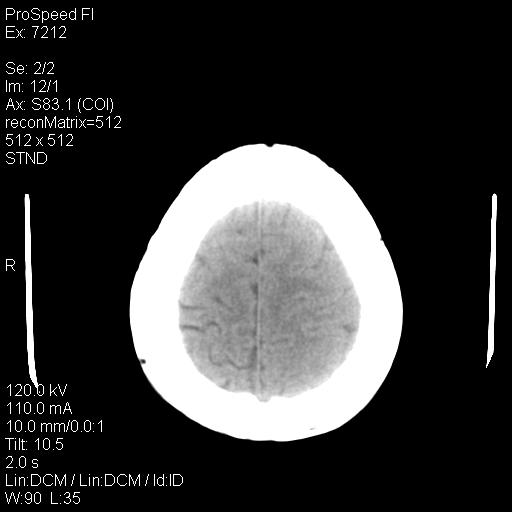

标题: CT18636:F 44Y,头痛三个月,左侧肢体麻木一周。临床诊断, [打印本页]

标题: CT18636:F 44Y,头痛三个月,左侧肢体麻木一周。临床诊断,

右额叶脑沟变浅,脑表面见新月形稍高密度影,考虑慢性硬膜下出血可能。

额顶骨多发穿凿样骨缺损区,不排除骨髓瘤等改变,进一步检查。

1)考虑左侧额颞部及右侧额部慢性硬膜下血肿(或硬膜下积液)。2)颅骨骨髓瘤不排除;建议行进一步检查。

1)右侧半卵圆中心腔隙性脑梗塞。2)考虑左侧额部慢性硬膜下血肿(或硬膜下积液)。3)颅骨骨髓瘤不排除;建议行进一步检查。